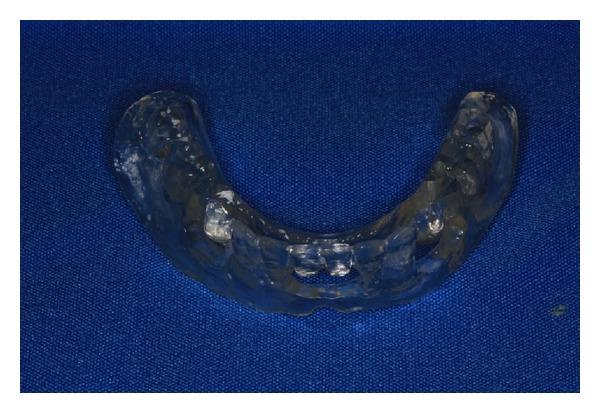

In mandibular edentulous patients, treatment based on immediate loading with rigid splinting in the mandible is well accepted; however, it is cost and time dependent, which sometimes limits this type of rehabilitation. To overcome these problems, the technique of immediate loading using a semirigid splinting extension system has been developed. Its advantages include low cost, technical feasibility, and reduced clinic time. This clinical report presents the applicability and the predictability of semirigid splinting of implants in the mandibular arch of an edentulous patient using a distal extension bar prosthesis system.

在下颌无牙患者中,基于下颌即刻负重并采用刚性夹板固定的治疗方法已被广泛接受;然而,这种方法成本较高且耗时,有时会限制此类修复方式的应用。为克服这些问题,已开发出使用半刚性夹板延伸系统进行即刻负重的技术。其优点包括成本低、技术可行性高以及临床时间缩短。本临床报告介绍了在一名无牙患者的下颌弓中使用远端延伸杆假体系统对种植体进行半刚性夹板固定的适用性和可预测性。